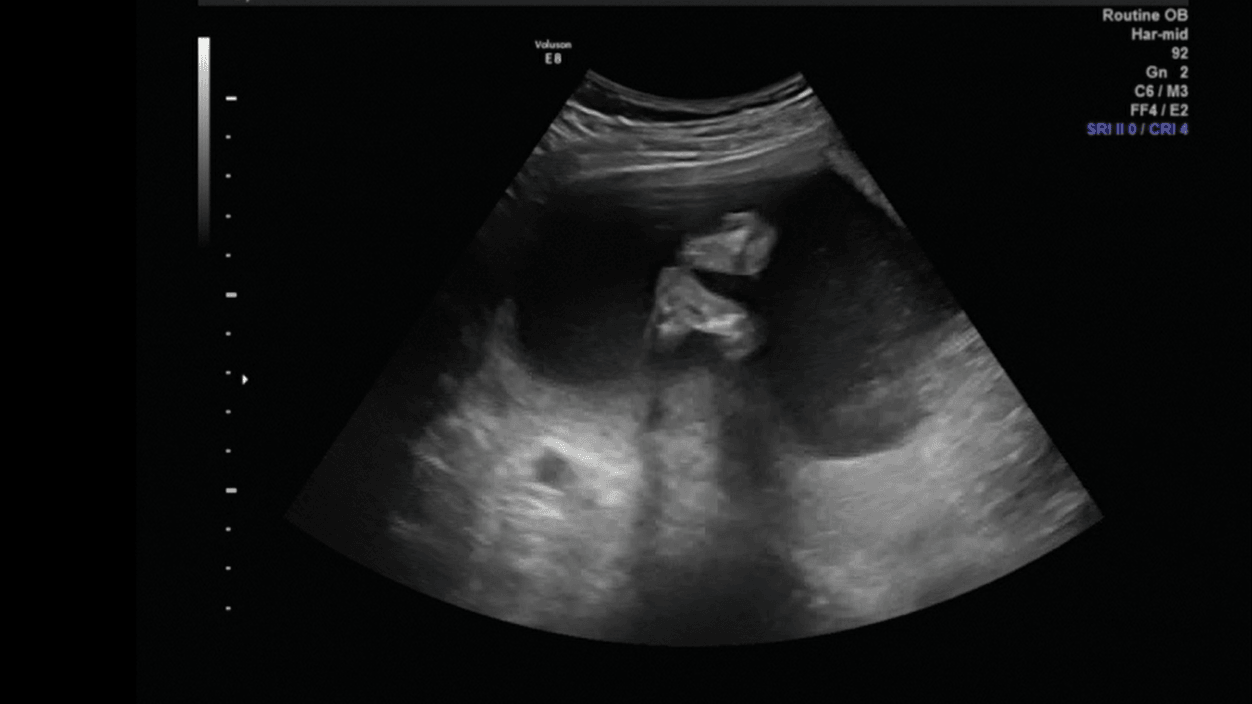

Wrzucę kilka fotek tutaj a resztę w wątku z usg

Nasz akrobata (stopa przy nosku)Zobacz załącznik 839724

Zobacz załącznik 839725

Stópki [emoji7]